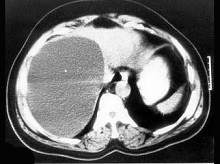

对无并发症的先天性肝囊肿的治疗,正确的是 ( ) PGJ-2093.jpg